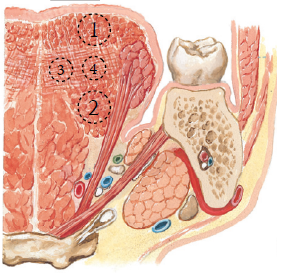

Nerve

運動

感覺

- 根部 taste/ general sense

- 後 taste/ general sense

- 前

- Taste: Chorda tympanic

- General sense: Lingual n

Hyoglossus m. 外側

- Lingual n.

- Hypoglossal n.

- Submandibular duct